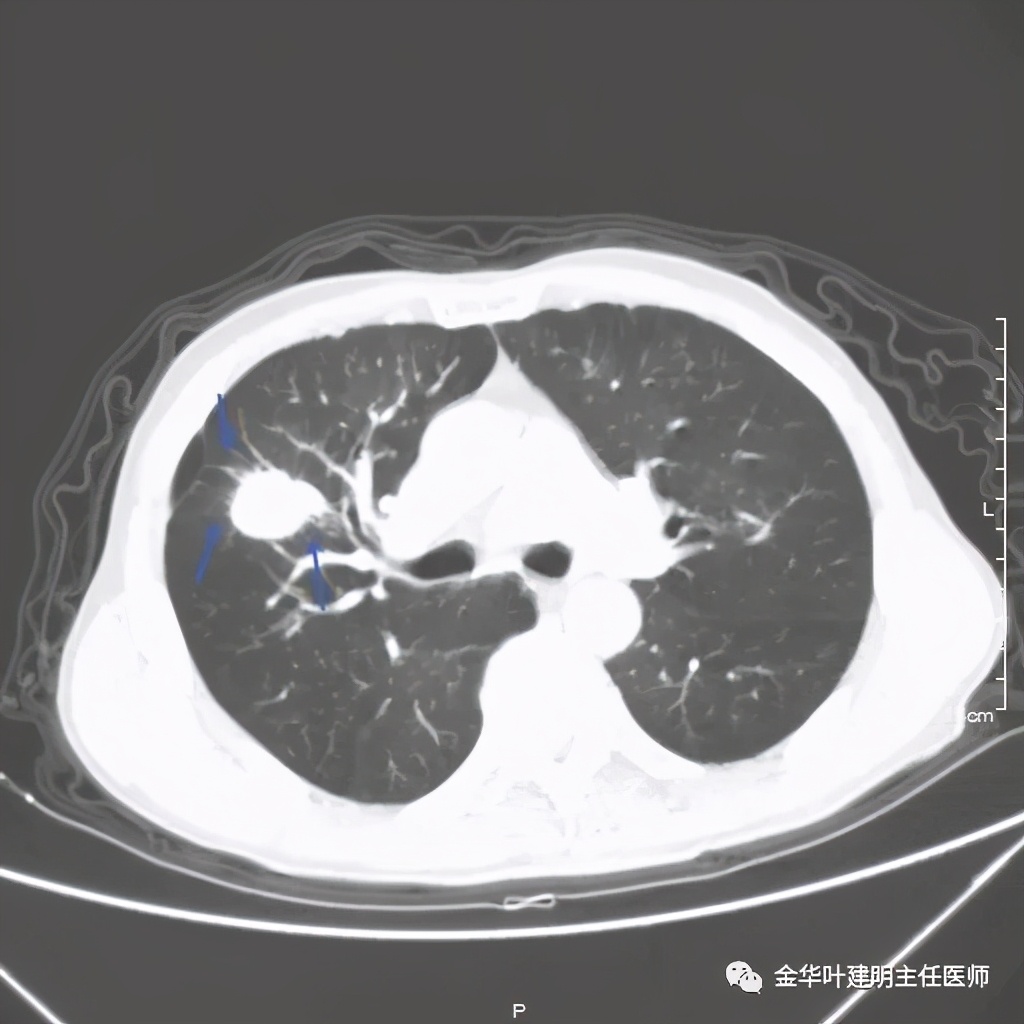

上图黄色箭头示穿刺针进入的地方,位置还是非常好的,应该容易穿到有价值的病变组织。但穿刺结果未见肿瘤:

上图是穿刺时的某个层面,病灶的细毛刺征比较明显(蓝色箭头),病灶的边缘是不平的,而且有细短的毛刺样突向周围肺组织,这可是恶性的特征

桔色箭头示病灶周围血管征明显,有较粗的血管进入病灶,较细的也有